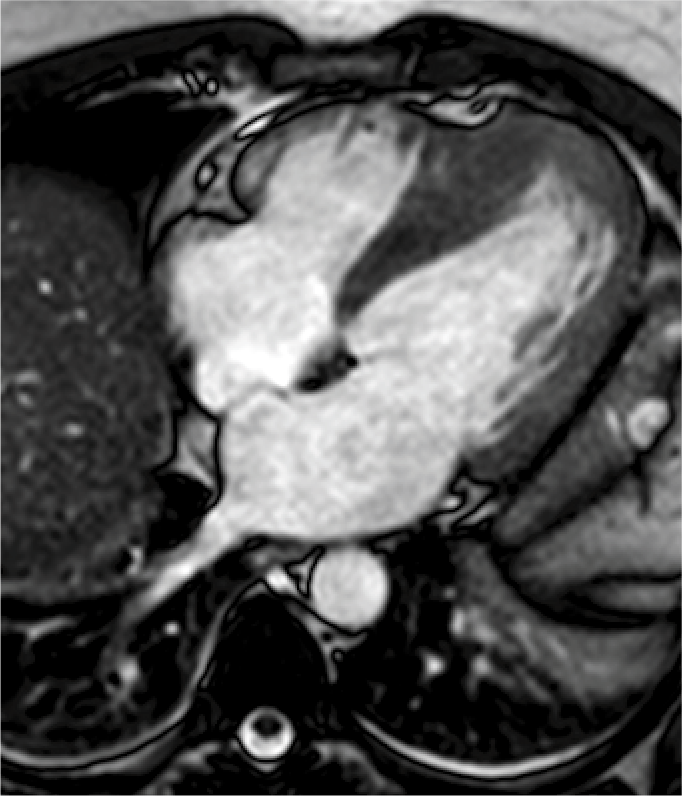

La resonancia magnética cardiaca es un una técnica de imagen que permite estudiar detalladamente y en una sola exploración la función y la estructura del corazón. Este auxiliar diagnóstico utiliza un potente campo magnético, sin radiación, para generar imágenes detalladas de las estructuras del corazón.

La resonancia magnética esta indicada en la evaluación de las cardiopatías congénitas tanto en el niño como en el adulto, en la evaluación de la perfusión miocárdica (resonancia cardiaca con gadolinio), de la función cardiaca, de las enfermedades del músculo cardiaco (miocardiopatías), tumores del corazón y del tejido que rodea al corazón (pericardio).

Este estudio es bien tolerado por la mayoría de las personas. El campo magnético no es dañino, pero puede causar el mal funcionamiento de algunos dispositivos médicos. La mayoría de los implantes ortopédicos no presentan riesgos, pero siempre debes informar al técnico de resonancia magnética si tiene algún dispositivo o metal en su cuerpo.